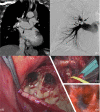

We present the case of a 78-year-old female undergoing pulmonary endarterectomy (PEA) because of suspected chronic thromboembolic pulmonary hypertension (CTEPH). During surgery firm black masses were encountered in the aortopulmonary window and on the cranial part of the right pulmonary artery (PA). After PA arteriotomy we visualized intraluminal black firm stenosing plaques at the orifices of the three right and of the left lingular and lower lobar branches. Since no dissection plane could be obtained the procedure was discontinued. Subsequent bronchoscopy visualized a submucosal dark black-blue discoloration in both main bronchi. Pathological analysis revealed anthracofibrosis, which could be explained by biomass smoke exposure in the past. We are the first to provide intravascular pictures and pathologic images of this very rare entity. Moreover, we report stenoses at the orifices of the three right-sided lobar and of the left-sided lingular and lower lobe arteries, in contrast to three previous reports that report on single locations caused by extrinsic PA compression from lymphadenopathy. Our case, however, suggests extension of fibrosis with anthracotic pigment into the PA wall. We conclude that in the absence of a clear history of exposure to carbon smoke and with consequently no diagnostic bronchoscopy, anthracofibrosis of the lungs may mimic CTEPH not only by external compression but also by extension into pulmonary vascular structures. PEA-surgery should not be attempted in these cases.